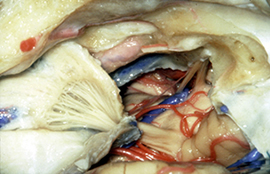

症例3) 31歳男性、延髄前面巨大舌下神経鞘腫

< 画像所見 >